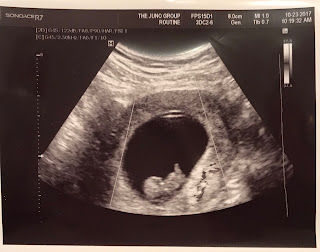

Our 8 week appointment was incredibly hard. I wanted to be excited so badly, but my mind kept racing with all the “what ifs.” I saw the ultrasound machine and my heart sank. So many painful memories of starring helplessly at a screen with vague images of our little one and listening to reports about all the things that were going wrong. Thankfully, they were able to find a heartbeat quickly and for a brief moment my mind was relieved.

It’s been a battle to resist the fear, yet with every passing day I’ve wanted to hope a little more that this time things would be different. Then this past Saturday I felt awful. And not in a good, normal pregnancy kind of way. I was very concerned that something was wrong. Thankfully we already had the appointment coming up so we did what we did so much of with Silas…. wait.

Monday morning came and we went to our appointment. My worst fear was confirmed when the doctor pulled up the image on the ultrasound machine. Where there should be a tiny flicker, there was none. The heartbeat was gone. I laid there. Numb. Helpless. Heartbroken. So similar to when Silas was born. There was absolutely nothing I could do. Another moment that reminded me how fragile this life can be. No guarantees. Nothing set in stone. Because I’m far enough along they scheduled a procedure for this Wednesday. To be honest, I hate this. I’m so disappointed. And, I’m terrified to go back to the hospital. But….. My reason for writing is two-fold. One, I want to leave a reminder to myself that even on the hardest days the Lord has been faithful. I remember with Silas I had made a mental list… “things I cannot do.” I can’t go to another appointment and face more bad news. I can’t face another day carrying a baby that will most likely die. I can’t handle a delivery with so many uncertainties... I can’t hand him over when it’s way too soon to say goodbye. I can’t walk out of this hospital with empty arms. I can’t deal with another day of sadness. I can’t… I can’t… I can’t…. Yet, God CAN. And He did. And He was there. And He WILL be here. Often a peace has come over me that I know is nothing of my own doing. As the Bible says, draw near to Him and He will draw near to us. Call to Him and He will answer you. Seek Him… and He will be found. And that friends, is something I cling to. He was the calm in that delivery room on January 9th. He will be with us tomorrow as we face another heartbreaking loss. He has been my comfort on days that seem quiet and uneventful…yet pain runs deep and unseen by others. But He sees. And He knows. And I believe He cares more than we can ever know. Secondly…. I have heard from so many since Silas died. Your stories. Stories of loss. Heartbreak. Infant death. Miscarriage. Divorce. Disappointment. Illness. Job loss. We all face brokenness in this world. I’m not here with all the answers. If anything, I probably have more questions than ever. But I feel I am (slowly) learning one thing. The Lord has this beautiful way of taking the broken and shaping it into something, dare I say…. good. I’m not naive enough to think that means a life free of pain. On the contrary, I more convinced that it’s the pain He allows to touch our lives that can provide an opportunity for us to know Him in a way that fulfills our deepest desires. Pain that enables us to understand His love more and experience the gifts He offers… Joy when we are surrounded by sadness. Peace when there should be none. Contentment when the things…. or people... we desire most are ripped away. This year has been full of challenges for us. And as I write this, there are tears. Partly because life can be so hard…but even more... because God is good. He is trustworthy, and He is pursing us. He longs for us and wants us to long for Him. This is an expert from a book that says it way better than I ever could…. ”She gave Him the kind of worship one can give only from a thin place--a place where the separation between this world and eternity seems to dissolve, a place where we believe and experience God’s love in a visceral way. My empty womb ushered me into that thin place, the place where I began to believe --not just say-- that God’s love is real. With every bleeding day, I was forced to reveal myself in pain, before His eyes. And that’s when I discovered how truly beautiful His eyes are. Only then could i pour myself out at His feet with unhinged, unembarrassed, extravagant devotion.” -Unseen by Sara Hagerty So I can say with a quiet and broken spirit…God is good. He is faithful. We would sure appreciate your prayers today and in the days to come. I’m thankful for those of you who have shared your stories with me. There is a strange comfort in knowing we are not alone in our suffering. So many of you have braved being real and shared the pain you have endured...and encouraged me to keep on going. I can't tell you what that has meant to me. 16 "Therefore we do not lose heart. Though outwardly we are wasting away, yet inwardly we are being renewed day by day. 17 For our light and momentary troubles are achieving for us an eternal glory that far outweighs them all. 18 So we fix our eyes not on what is seen, but on what is unseen, since what is seen is temporary, but what is unseen is eternal." 2 Corinthians 4:16-18 Longing for the unseen so very much. Especially two little faces that I am so incredibly anxious to see.